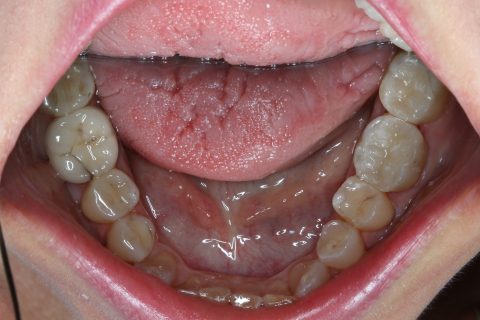

Composite Füllung

| Vorteile | gutes Aussehen, gute Haltbarkeit bei kleinen bis mittlelgroßen Füllungen |

| Nachteile | hoher Aufwand, absolute Trockenlegung für ein dichtes kleben am Zahn unerlässlich, d.h. nicht möglich bei blutendem Zahnfleisch u. sehr tiefen Füllungen |